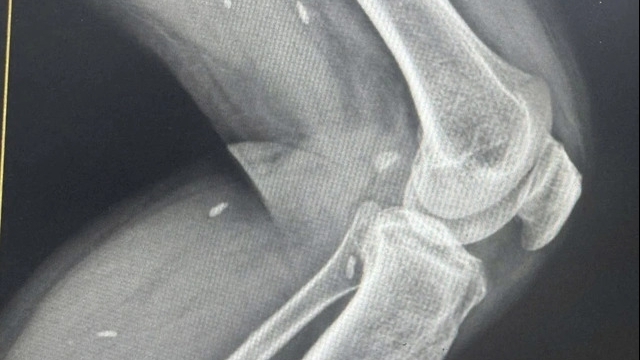

Nếu như trước đây, y học cổ truyền đề ra bốn bước: Vọng - Văn - Vấn - Thiết, tức là Nhìn, Nghe, Thăm hỏi và Bắt mạch kê đơn thuốc; thì hiện nay việc khám, chẩn đoán, điều trị bệnh đều dựa vào những tiến bộ của y học hiện đại. Thông qua những kỹ thuật cận lâm sàng như xét nghiệm kết hợp chẩn đoán hình ảnh, siêu âm, thăm dò chức năng… cho phép bác sỹ nắm bắt chính xác bệnh tình từ đó đưa ra liệu trình điều trị, kê đơn phù hợp nhất.